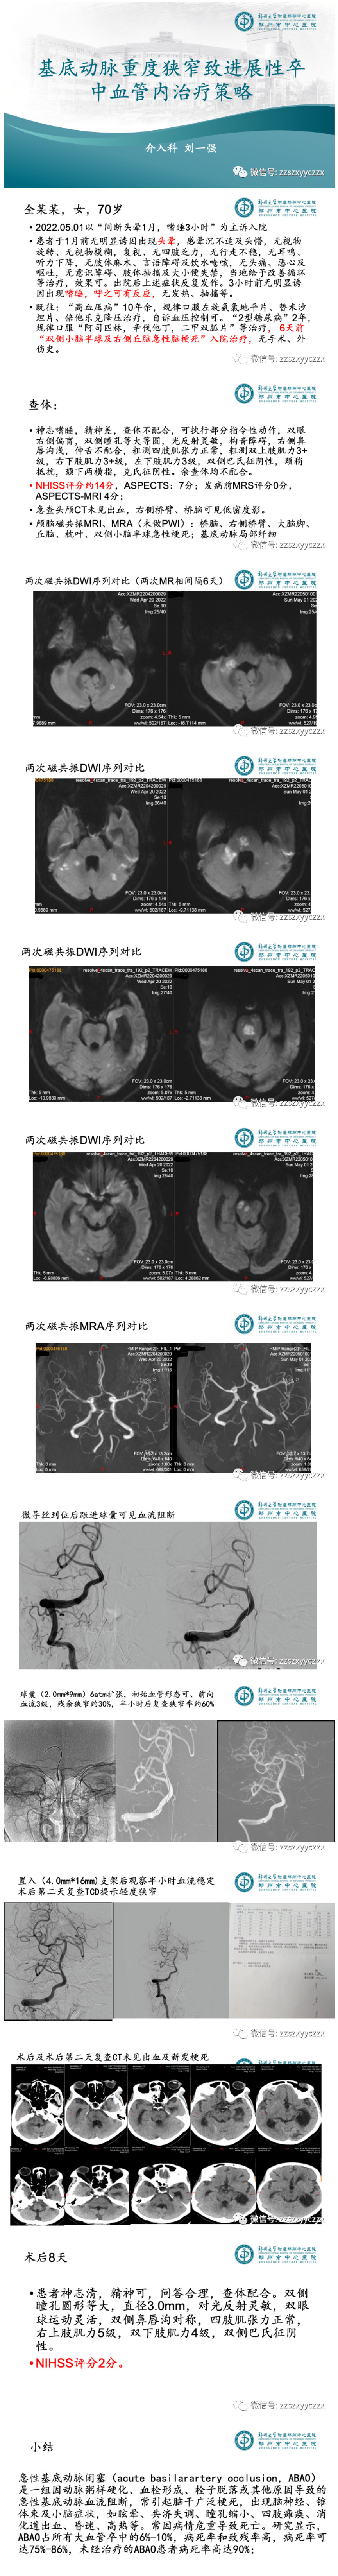

作者:郑州市中心医院卒中中心 刘一强

本文和大家分享1例基底动脉重度狭窄致进展性卒中的血管内治疗经过。